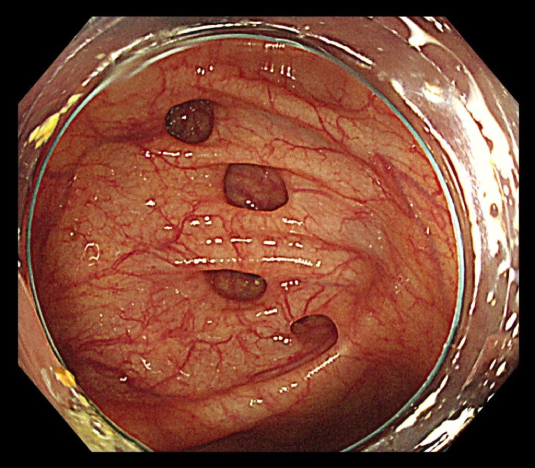

大腸憩室症の大腸内視鏡検査写真

【大腸憩室症の大腸内視鏡検査写真】(OLYMPUS EndoAtlasより引用)